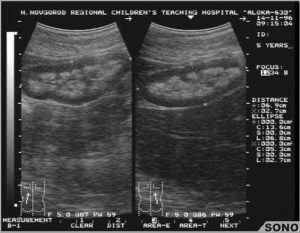

Образования, вызывающие сверхсильное отражение, чаще возникают в паренхиме и почечных пирамидах и могут проявляться на экране белыми точками и пятнами различных размеров (см. фото).

На мониторе при ультразвуковом обследовании высвечивается белое пятно, которое является лишним элементом структуры, и врач сразу определяет наличие или отсутствие акустической тени. Это является определяющим моментом для установления плотности гиперэхогенного включения.

Метод УЗ-исследования основан на степени отражения ультразвука от тканей различной плотности. Гиперэхогенность – это усиление акустической тени, то есть на практике это значит, что структура органа имеет высокую плотность и хорошо отражает ультразвук. На мониторе это выглядит как более светлая, почти белая область.

Есть также такое понятие при УЗ исследовании почек, как синдром выделяющихся пирамидок. При этом повышается эхогенность коркового слоя и пирамидки выглядят заметно темнее, выделяются.

В норме эхогенность коры сравнима с паренхимой печени, ее повышение указывает на серьезное нарушение в работе почек. Это может быть острый гломерулонефрит, острая почечная недостаточность различной этиологии.

У новорожденных детей и до 3-летнего возраста такой симптом считается нормой. Кора выглядит гиперэхогенной, поскольку количество нефронов в почке закладывается внутриутробно, корковый слой у плода еще недостаточно развит, поэтому плотность повышена. У новорожденных соотношение коркового и мозгового вещества составляет 1 к 5, а у взрослых 2 к 3.

При УЗИ врач диагност рассматривает не только пирамидки, но и основные показатели почек. В норме они должны быть правильно, симметрично расположены, иметь ровный контур гиперэхогенной капсулы. Измеряются их размеры, положение и подвижность на вдохе. Эти показатели позволяют оценить общее состояние, наличие дефектов.

Затем рассматривается структура и строение паренхимы. Появление крупных образований высокой плотности вызвано образованием камней при мочекаменной болезни или развитием очагового воспалительного процесса.

Участки низкой плотности могут возникнуть при кисте почки, гематоме.

Особое внимание надо обратить на яркие, белые включения, которые указывают на наличие в почках склеротической ткани, кальцификатов и псаммомных телец (белково-жировые комплексы), присущих злокачественным новообразованиям.